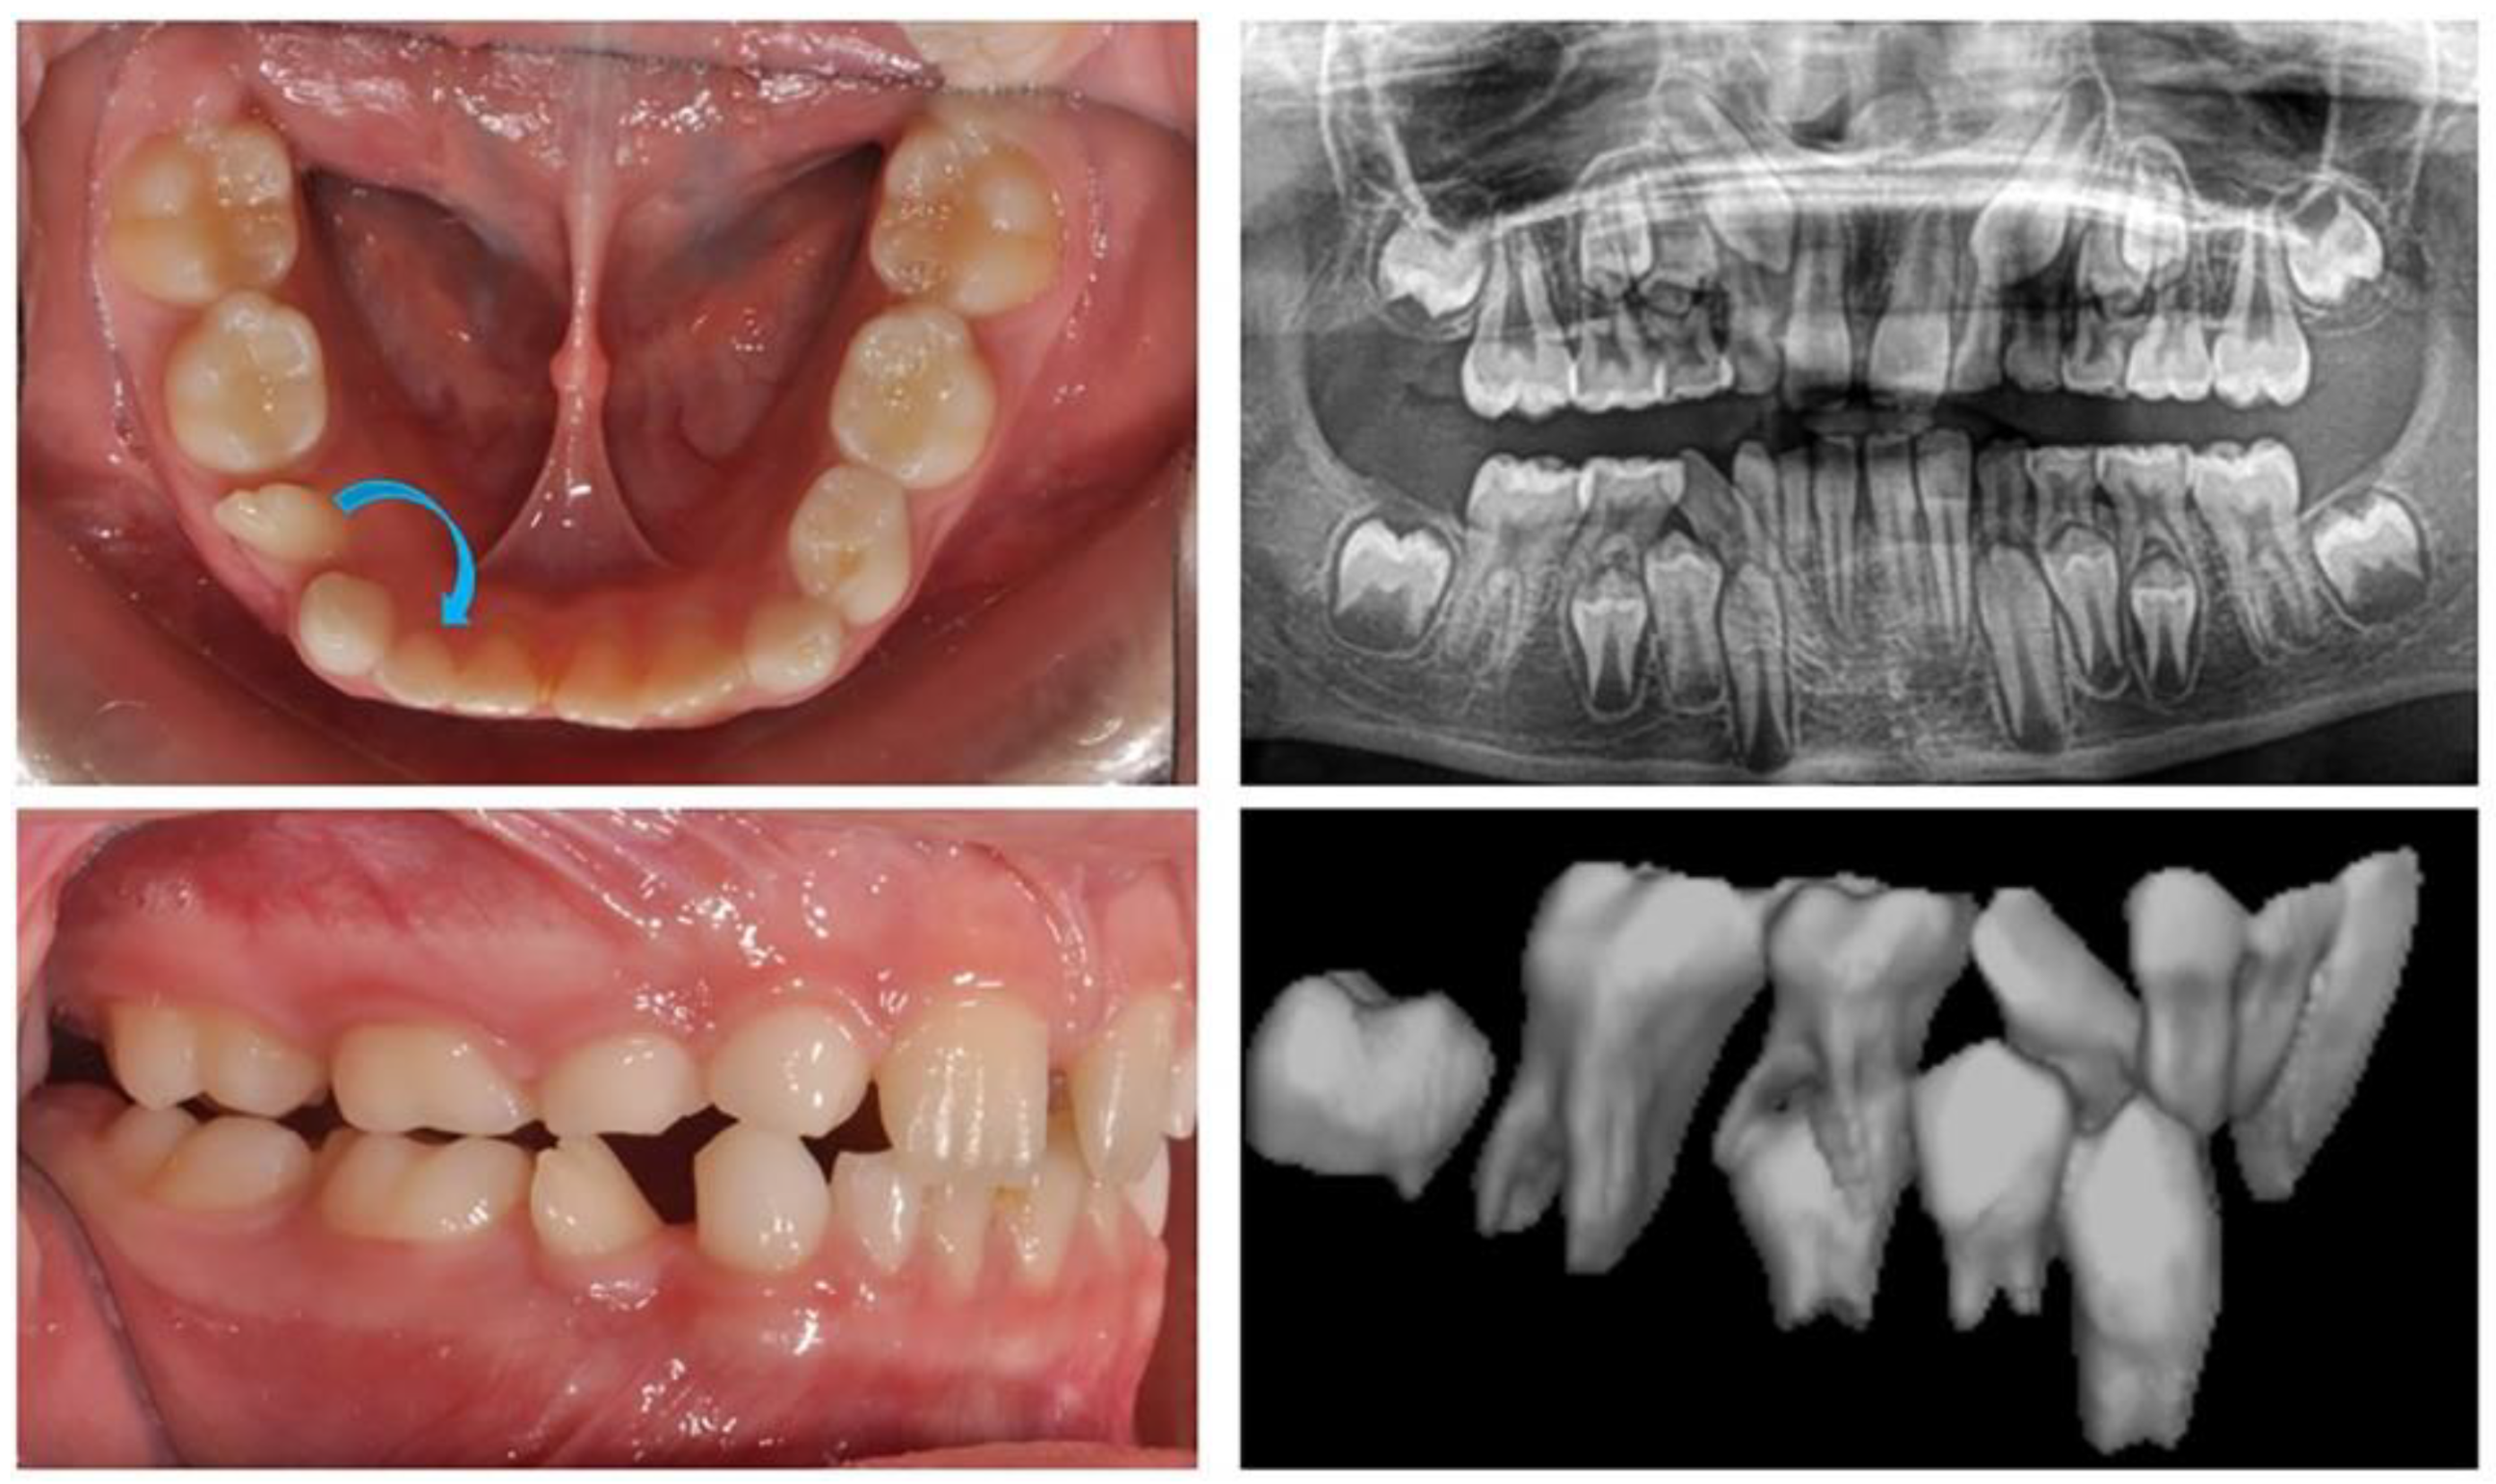

2.2.1. Clinical Case 1–Ectopic Eruption of Lower Right Lateral Incisor

The first clinical case is that of an 8-year-old girl with an ectopic eruption of the lower-right lateral (42) in the area of the first temporary molar. In the lower dental arch, the temporary right lateral incisor and canine are in preserved positions. After an X-ray examination, hypodontia of the upper laterals was established in the upper dental arch. A well-developed and normally positioned germ of right canines and premolars in the lower was found (Figure 1). In this early phase of mixed dentition, the ectopically erupted lower-right lateral incisor should be positioned in its normal location. This will prevent future canine transposition or canine retention due to the mechanical barrier that the lateral presents. At the same time, it is important to preserve the perimeter of the dental arch in the case of the premature exfoliation of the temporary canine.

Figure 1.

Oral clinical status and X-ray examinations of a patient with an ectopic eruption of the lower-right lateral (42) in the area of the first temporary molar. The blue arrow show the natural position of lower right lateral incisor.